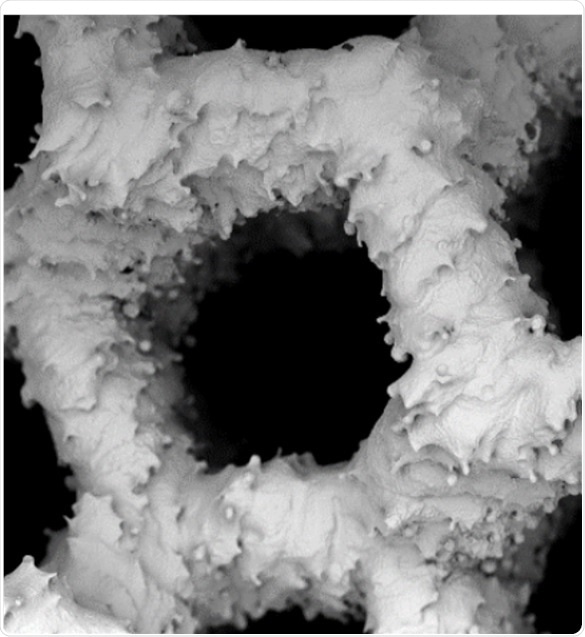

In another study on skeletal injuries and tissue engineering conducted in Poland, the application of titanium scaffolds in tissue engineering2 was evaluated. It is possible to replace bone loss using tailored titanium scaffolds, which are supporting net shaped structures, created by additive manufacturing. It is essential to remove these additives during a chemical treatment used for polishing the scaffolds.

The effect of this chemical polishing on the porosity and morphology of the scaffolds was studied using a SEM. The size of the chemical particles was determined using the ParticleMetric software and the morphology before and after polishing was shown by the subsequent SEM imaging. The study was successfully completed using the PoroMetric software using which the effect of chemical polishing on the scaffold’s pores was visualized and measured by the researchers.

SEM images of scaffoldSEM images of scaffold

Figure 2. SEM images of scaffold. Adapted from 1.